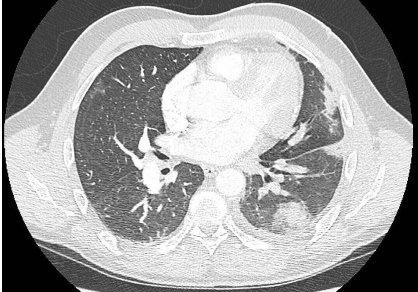

復(fù)查胸部 CT 提示左肺動(dòng)脈充盈缺損較前擴(kuò)大,伴分支血管充盈缺損影像(圖 1)。左肺邊緣呈片狀楔形陰影,提示肺梗死(圖 2)。